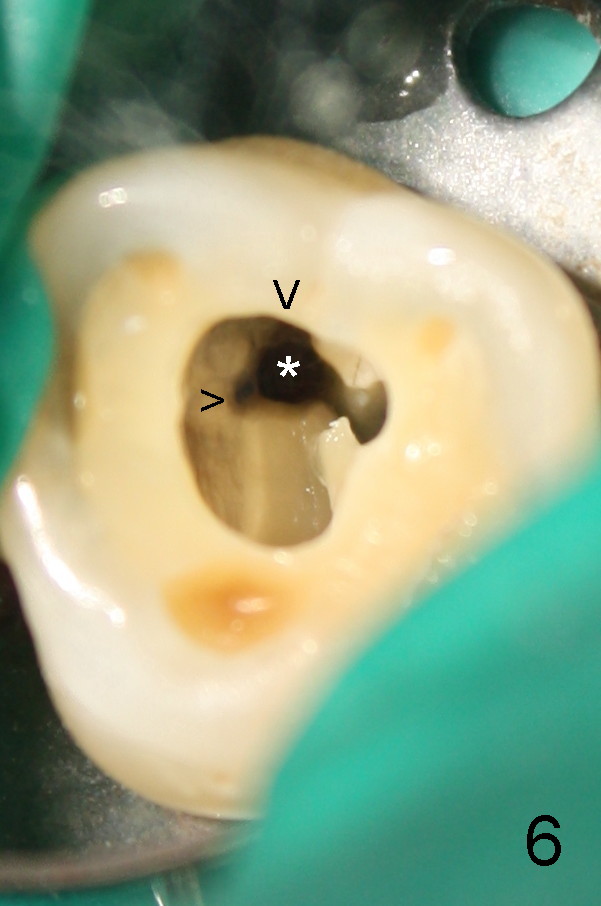

50岁男士有严重牙周炎(图一(2009年拍摄):二号牙(左上七)最终拔除(与图二对比)),最近三号牙(左上六)冷热痛,而且不能咬东西,三号牙多处牙周袋深,根尖片显示远中颊侧和腭侧根尖阴影(图二箭头),初步诊断:牙周牙髓综合症,需要根管治疗以及牙周手术,还可能保留不了。开髓表明活髓,近中颊侧和远中颊侧(DB)根管口很接近(参考图一图二),扩大(30/.04)后并表现不出来(图五至图七),开始近中根管口好像比较接近腭侧根管口,以为是MB2,使用Piezo超声波/diamond tip在MB(图六*)颊侧和近中寻找另外一个根管(箭头),但不成功。腭侧根管扩大到40/.06,匆匆忙忙插入主牙胶尖,拍摄根尖片(图三),显示远中颊侧以及腭侧(P)牙胶尖在相应牙根正中,但是近中颊侧并不是这样(图四=图三+MB牙根和牙胶尖轮廓),这说明还存在另外一个根管。经过再次合适扩大(crown down),腭侧牙胶尖进入更深地方(临床上),这时病人已经坐立不安了,paper points吸干根管后,拍摄图五至图七,暂封。由于病人还缺失好几颗牙齿,劝他去拍摄CT。今天术后第五六天,打电话给他,他很高兴,说冷热痛消失,牙齿也牢靠多了,但是还没去拍摄CT。下周三他回来完成根管治疗。

如果他还没有CT,我该怎么在没有外科显微镜下找遗留根管呢?MB和P根管口之间的确有一个沟(map),但是非常光滑(图五至图七),能找到根管口?还是往原来MB根管口颊侧探索?图三/图四暗示MB1还没有被发掘,对吗?MB2存在吗?